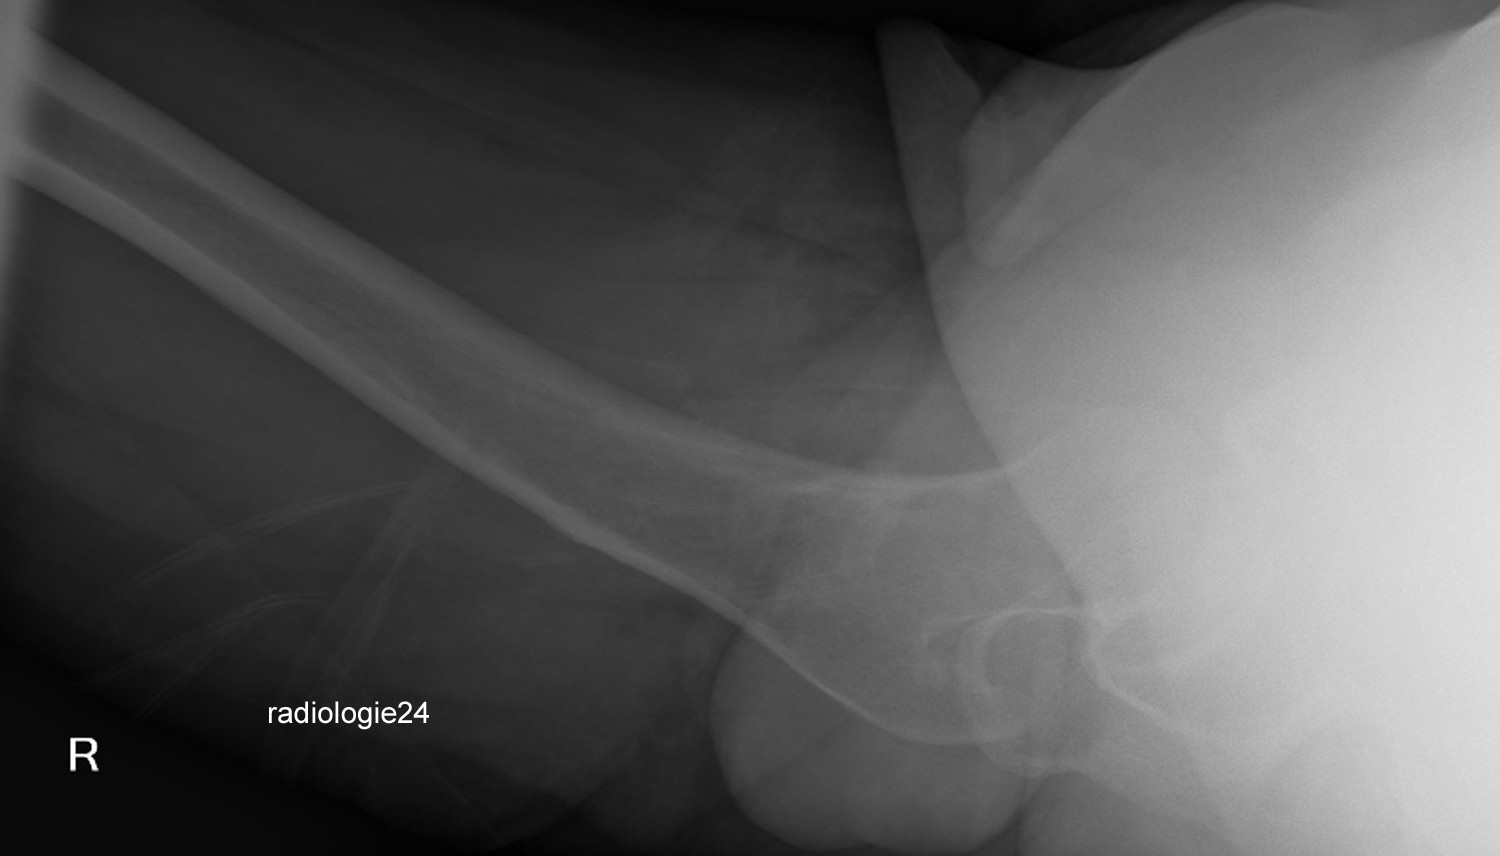

Röntgenfall des Monats Oktober 2018 mit Auflösung

34 jährige Patientin. Progrediente Schmerzen in beiden Hüftgelenken. Z.n. Sturz. Ihre Diagnose? Weitere radiologische Diagnostik notwendig?